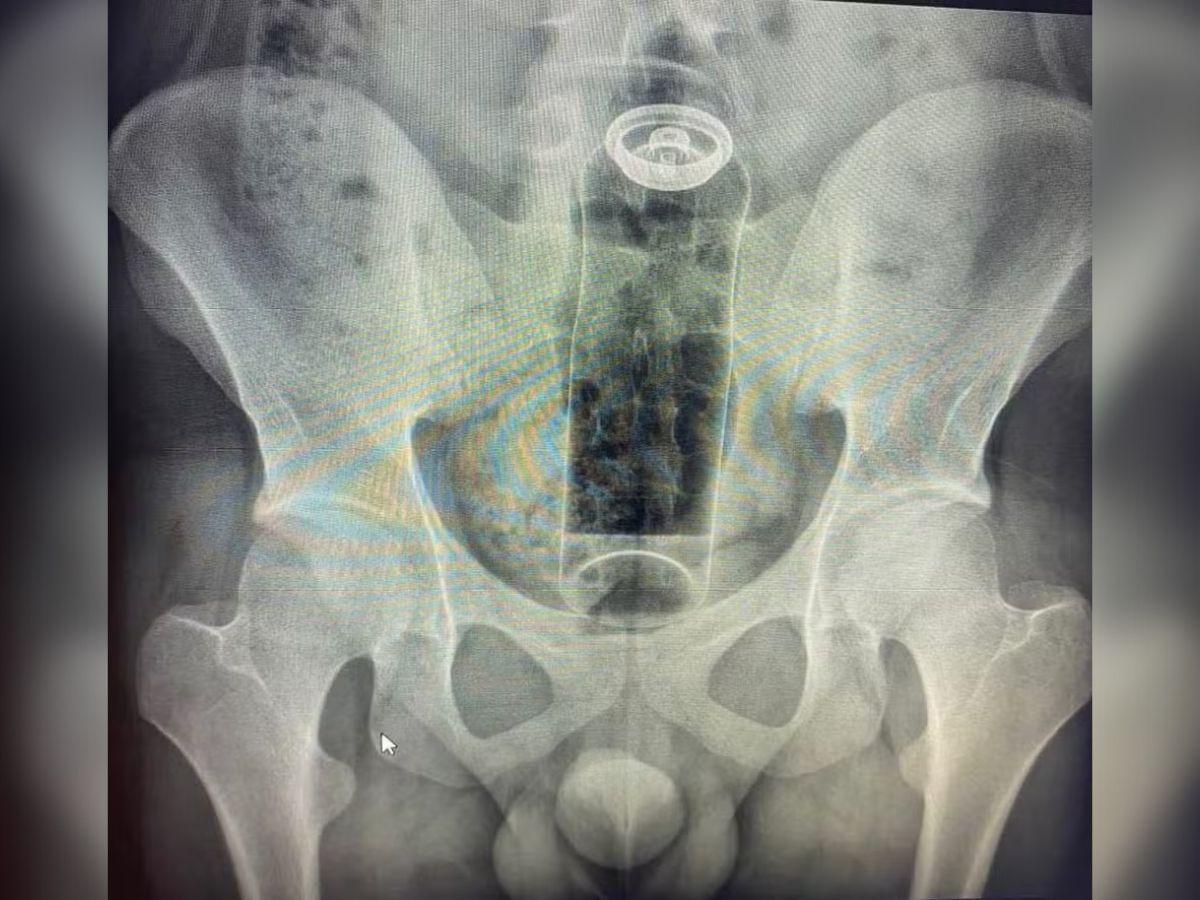

Jovem de 19 anos é internado às pressas para retirar desodorante preso no reto

Uma “brincadeira” íntima terminou em caso de emergência médica para um jovem de 19 anos, que precisou ser internado para retirar um frasco de desodorante que ficou preso em seu reto. O rapaz buscou ajuda hospitalar após perceber que o objeto havia migrado para a parte interna do intestino, tornando impossível a remoção manual em casa.

O incidente ilustra um risco real da anatomia humana: a região do reto possui movimentos involuntários (peristálticos) e pode criar um vácuo que acaba “sugando” objetos para cima. Quando itens inadequados, sem base de segurança, são introduzidos, eles podem ficar retidos rapidamente.